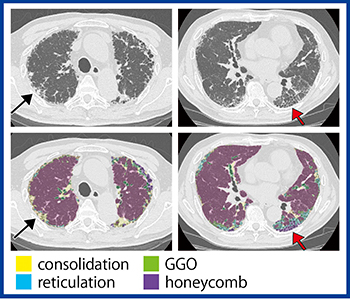

症例1(図1)は,70歳代,男性,IPFであるが,「QZIP-ILD」にて蜂巣肺(↑),網状病変,すりガラス状陰影(GGO),胸膜下の線維化に対するコンソリデーション(↑)がそれぞれ分類できている。「QZIP-ILD」では,3D表示のほか,肺葉ごとの結果を表示することも可能である(図2)。

図1 IPFの「QZIP-ILD」による解析結果(症例1)

図2 「QZIP-ILD」による肺葉ごとの解析結果(症例1)